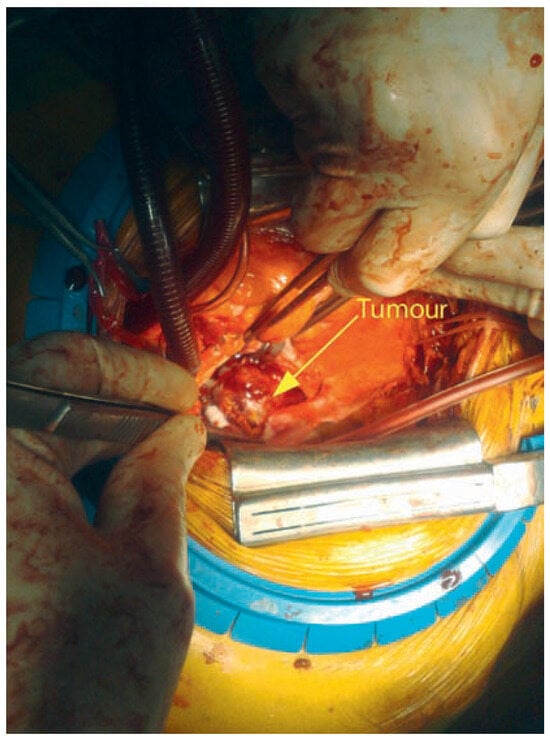

Clinical status showed: BP 150/65 mm Hg. Pulse regular at 82 beats per minute. Peripheral oedema was absent. Several peripheralsigns of aortic regurgitation were noted and a 3/6 protodiastolic murmur was present. Aortic valve replacement was decided and pre-intervention investigations were planed. Transthoracic echocardiography confirmed the aortic regurgitation grade III with mild dilatation of the left ventricle. Thoracic CT scan showed a 30 mm mass located within the left posterior wall (Figure 1). Transoesophageal echocardiography confirmed the location and dimensions of the tumour (Figure 2) and showed in addition involvement of the left atrial wall. Resection of the mass was performed during valve replacement (Figure 3). A 3 cm friable mass attached to the posterior wall of the atrium was easily removed. Reparation of the atrium was performed and a 23 mm aortic artificial valve was implanted. The outcome was uneventful. Histological and immunohistochemical examination conclude to a benign tumorous process compatible with the diagnosis of glomangiopericytoma (myopericytoma) (Figure 4). This was an unexpected diagnosis since to our knowledge it is the first case of cardiac benign haemangiopericytoma reported and secondly because of the patient’s history. A post irradiation tumour would have been more probable. Haemangiopericytoma is a rare tumour. The few one located in the heart were malignant.

Figure 3.

Intraoperative view at the time of mass removal (head of the patient on the left).